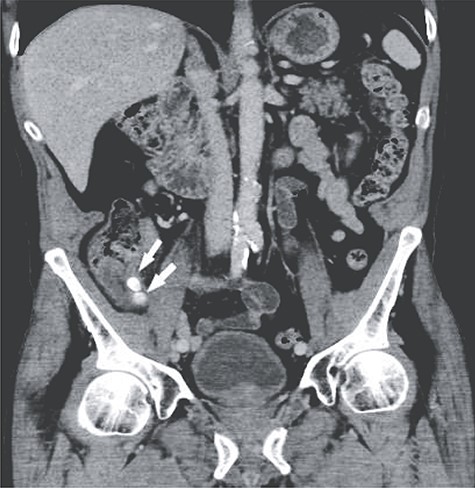

A 66-year-old male patient who had undergone bilateral blepharoplasty 3 days earlier was referred to our acute care surgical service with a 24-hour history of increasing right lower quadrant pain accompanied by nausea, vomiting and anorexia. Clinically he was found to be afebrile with a soft abdomen and focal tenderness at McBurney’s point. Significant laboratory investigations revealed a leukocytosis of 13.0. A CT scan of the abdomen confirmed the diagnosis of appendicitis with an impacted appendicolith at the appendicular outlet and a number of additional appendicoliths distributed along the length of the appendicular lumen (Figs 1–2). The patient was surgically consented for a laparoscopic appendicectomy with intraoperative video recording. At laparoscopy an inflamed and focally necrotic appendix was located coiled over the cecum (Figs 3–4). The appendectomy was completed without complication, and the specimen longitudinally transected in the operating room prior to pathological submission. This revealed four appendicoliths within the lumen, all measuring over 5 mm at their smallest diameter (Fig. 5). Pathology confirmed acute suppurative appendicitis with transmural necrosis, with the appendicoliths described as faeculent in origin. The patient’s post-operative recovery was uneventful.

Coronal view showing two of the larger appendicoliths at the appendix base (white arrow).